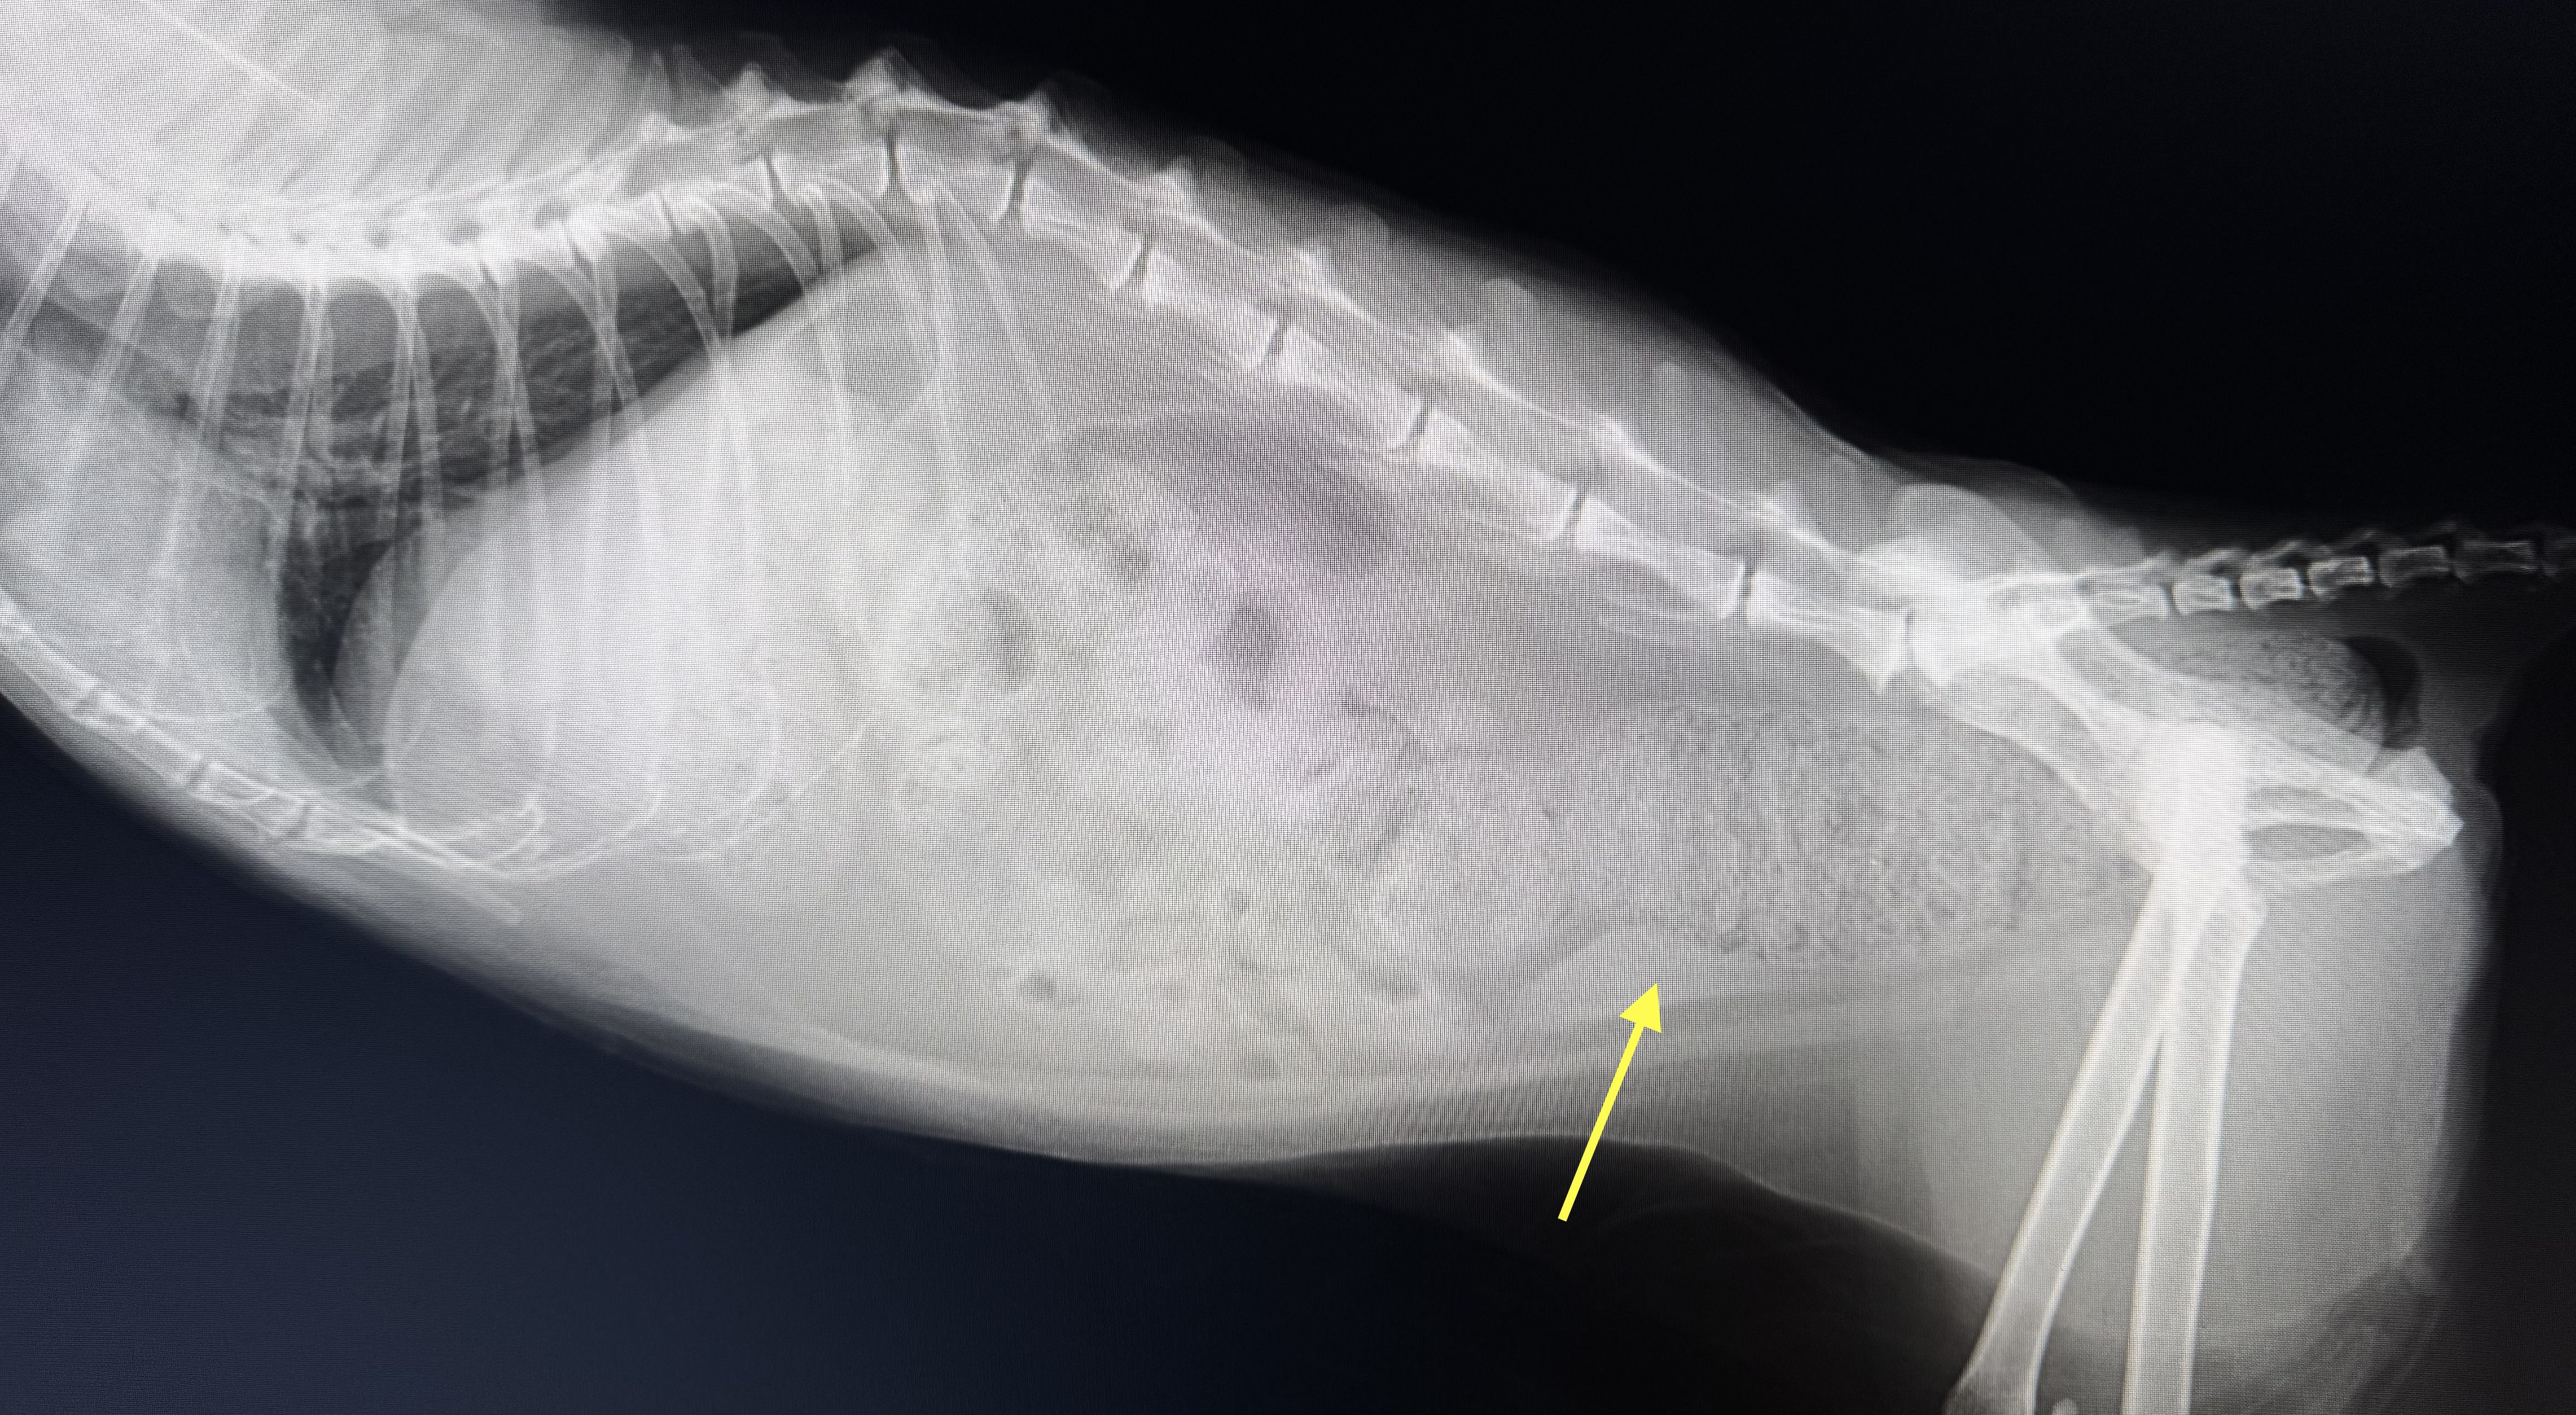

この写真は便が出なくなって、きばっていることを主訴に来院された13歳の日本猫の腹部レントゲン写真です。黄色矢印のところに大きな糞便の塊があることがわかります。骨盤(腰の骨)と比べて、そのスペースを出るか出ないかの大きさになっています。このような子は巨大結腸症と言われる病気になっており、大腸の運動が低下して、排便が滞り、大腸内に大量の便が貯留してしまうことになります。食欲も減退し、嘔吐が見られることもあり、早急に大腸内の糞便を取り除くために、浣腸や摘便処置が必要になります。この子はその後可溶性繊維を含む、専用の病院処方食に切り替えることで排便を促すことに成功し、今や20歳を超えるまで元気にしています。